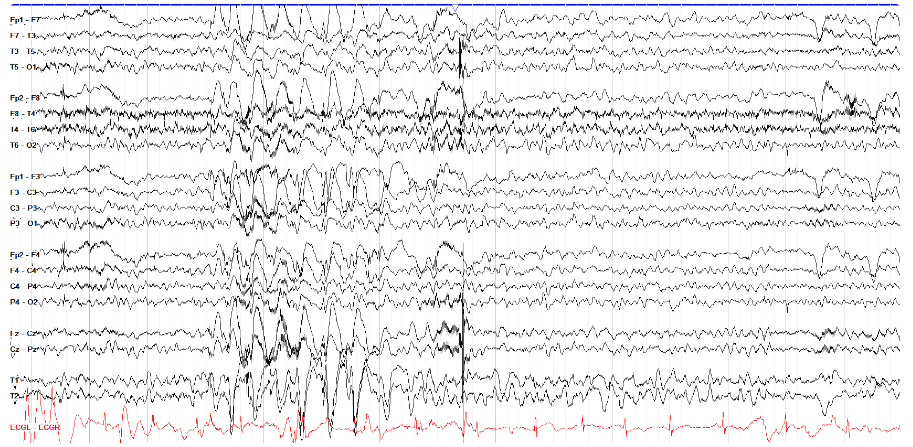

舌下伪影经常但不一定与咀嚼伪影一起出现。它由舌头的运动引起,并表现为较慢的、弥漫性的德尔塔频率活动。

注意,在下面的示例中,所有描记都具有本质上相同的运动——对于慢波睡眠之类的东西来说,这很有组织性,虽然发作模式肯定会导致这种节奏,但在这一页上没有证据表明癫痫发作特征随时间或地点的演变。

关于舌头运动伪影的一个值得注意的点是它是可重复的——你可以要求患者移动舌头,或者说“la la la”(又名舌音素),看看脑电图上是否显示出相同的模式。